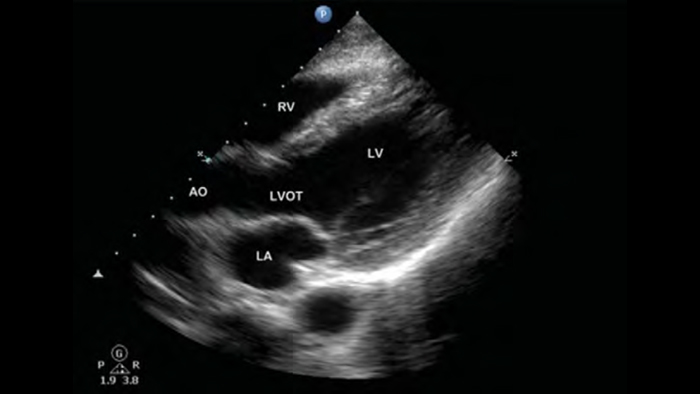

Lumify handheld ultrasound for anesthesiology helps you clearly visualize border definition with your needle placement, surrounding nerves, vessels and fascial planes.

Lumify helps you clearly visualize needle placement, surrounding nerves, vessels and fascial planes.

Lumify S4-1 broadband phased array transducer

• 4 to 1 MHz extended operating frequency range

• 2D, color Doppler, M-mode, advanced XRES and multivariate harmonic imaging

• High-resolution imaging for abdominal and cardiac applications: Cardiac, OB/GYN, Lung, Abdomen and FAST imaging preset optimizations